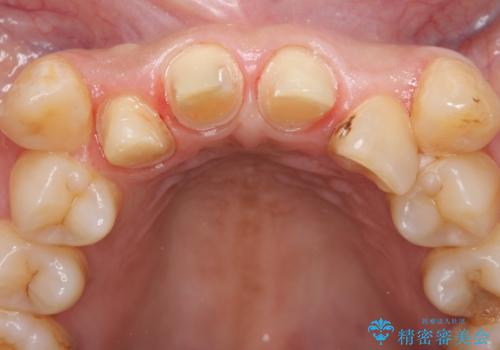

右上2は歯の神経が死んでおり、根尖病変を認めたため根管治療を行いました。

その後右上1,2番目及び左上1番目の歯に対してオールセラミッククラウンによる補綴を行いました。

- オールセラミッククラウン…¥100,000×3、仮歯…¥10,000×3、ファイバーコア…¥20,000費用は治療当時の料金となります